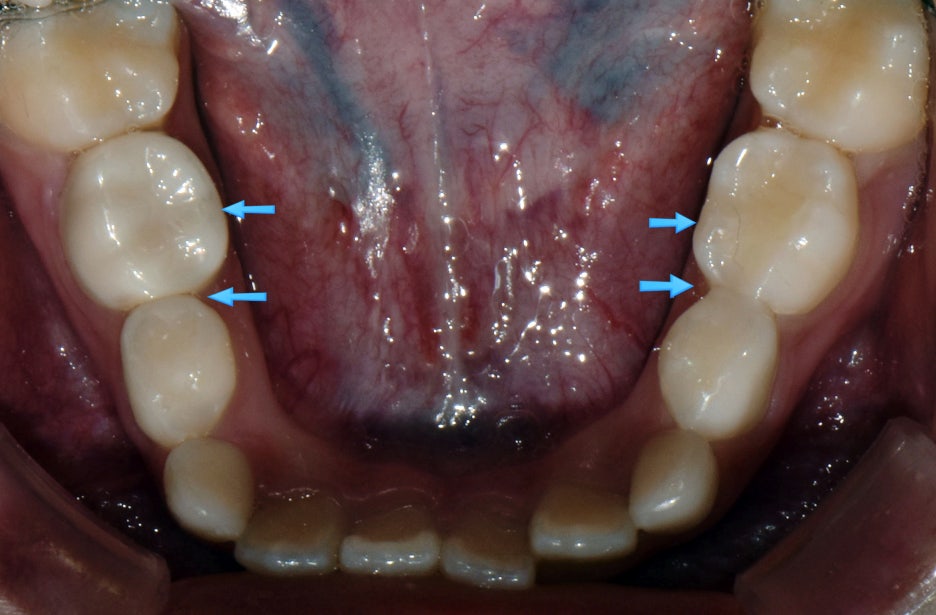

단 것 좋아하는 둘째 아이의 경우도 마찬가지로 수면치료 했습니다.

앞니, 어금니 모두 레진치료 했네요...^^;;

둘째 아이도 겁이 많은 아이지만 치과에 안좋은 기억이 전혀 없으며 이제는 초등학생이 되어 예쁜 영구치앞니로 모두 교환했습니다.

치료는 수면치료 하에 모두 마치고 이제 교정중인 둘째입니다.